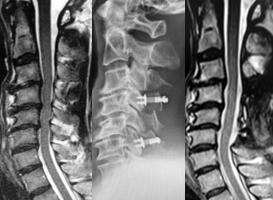

(左)術前のMRIでは、全体的に脊柱管内の狭窄があります。(中)片開き式脊柱管拡大術を施行し、金属性のプレートで椎弓を固定しています。(右)手術により脊柱管が拡大され、神経症状が改善しています。

手術前のMRIでは、第6/7椎間の椎間板が脊柱管へ飛び出し、脊髄を強く圧迫しています。 -

手術により、飛び出した椎間板を前方から摘出し、人工スペーサーと金属製のプレートなどで上下の骨を固定しました。術後、神経症状は著明に改善し、MRIでも脊髄の圧迫が解除されています